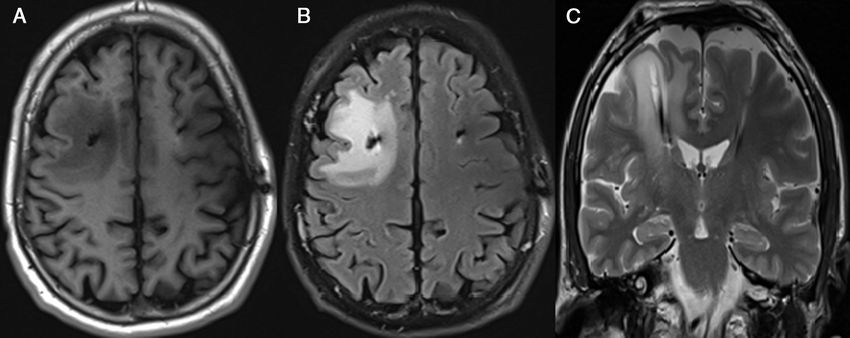

El edema cerebral persistente es una condición médica grave caracterizada por una inflamación continua del cerebro debido a la acumulación de líquido en los tejidos cerebrales. Esta hinchazón impide que el cerebro funcione con normalidad y puede provocar daños neurológicos severos o incluso la muerte si no se trata de manera oportuna.

A diferencia del edema cerebral agudo, que puede remitir con tratamiento, el edema persistente se mantiene a lo largo del tiempo, indicando que hay una lesión cerebral sostenida o progresiva, como podría ocurrir tras un traumatismo craneoencefálico severo, un derrame cerebral o una infección del sistema nervioso central.

Esta condición ejerce presión dentro del cráneo (presión intracraneal elevada), lo que compromete la circulación sanguínea y la oxigenación del cerebro.